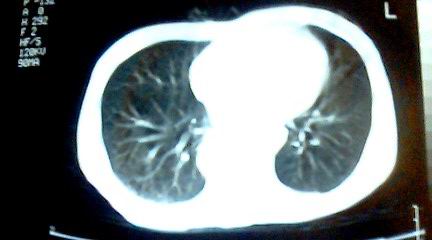

标题: CT25218:请教!胸部CT,胸8椎体骨质破坏,伴周围软组织肿。 [打印本页]

标题: CT25218:请教!胸部CT,胸8椎体骨质破坏,伴周围软组织肿。

患者,女41岁,肢体乏力。

两肺上叶继发性肺结核;胸椎结核并椎旁寒性脓肿形成。

两肺上叶继发性肺结核;胸椎结核并椎旁寒性脓肿形成